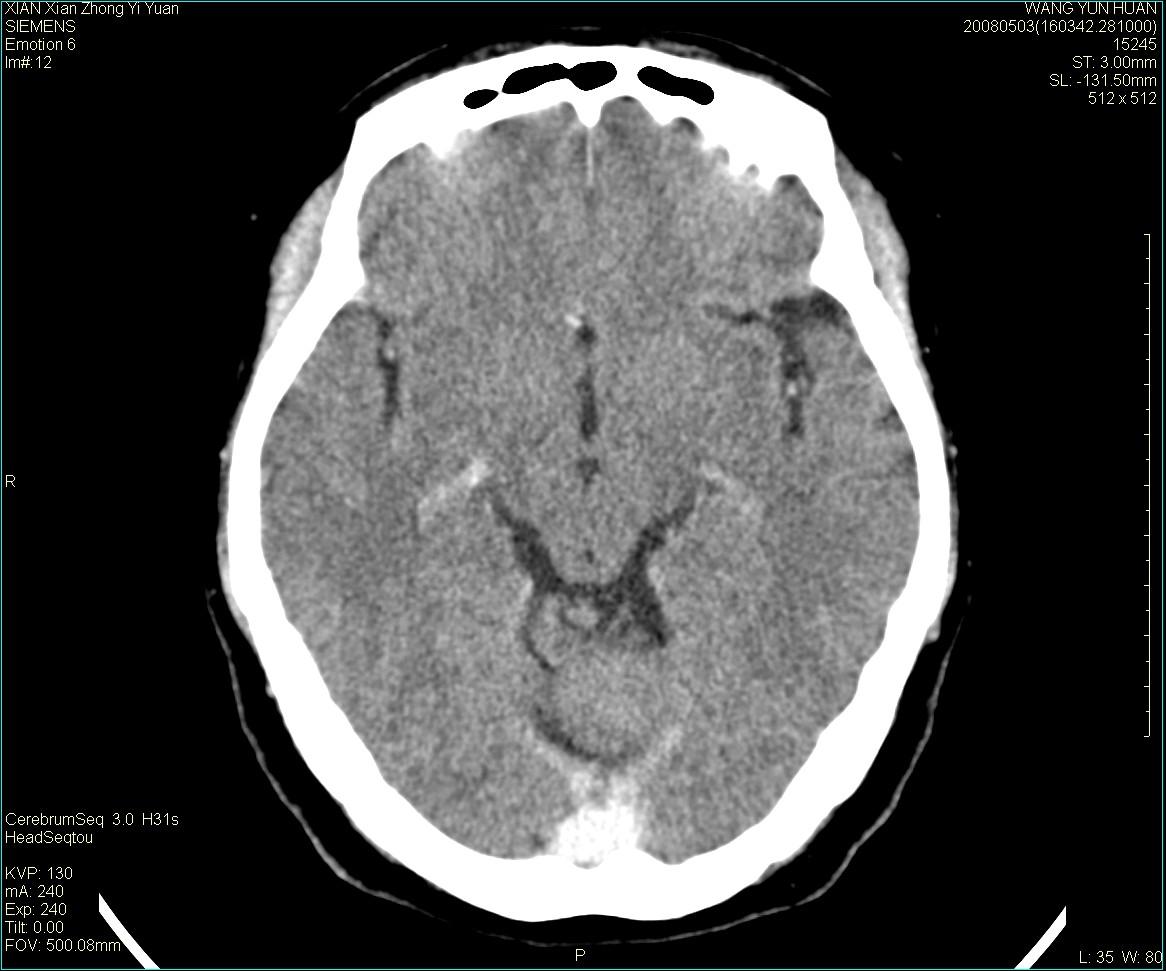

标题: CT13219:(补充强化)请会诊,患者女,60岁,头晕,大家看 [打印本页]

标题: CT13219:(补充强化)请会诊,患者女,60岁,头晕,大家看

病灶显示轻度强化,ct增加4hu左右,大家看是什么肿瘤.

强化后动脉期及延迟2分钟,五分钟图像

小脑蚓部囊型肿块,内有实性结节及钙化点。增强后囊壁及结节轻度强化。

考虑蚓部星形细胞瘤(ⅱ级可能性大)。

小脑蚓部肿块,周围无明显占位效应及水肿带,增强轻度强化,考虑低分级星形细胞瘤。